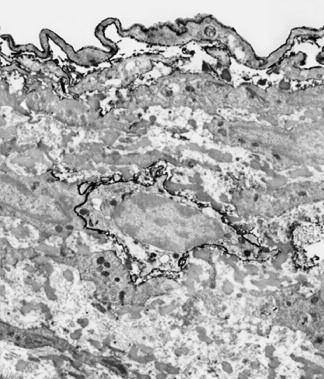

La foto nella pagina a fianco mostra una sezione trasversale al microscopio del fegato di un paziente con ‘leucemia linfatica’. Ciascuno dei piccoli puntini viola nella foto è un globulo bianco (in questo caso linfocita) che ha invaso il tessuto del fegato (aree rosa).

Considerando l’enorme quantità di questi puntini viola e il numero di enzimi che assimilano il collagene che ciascuno produce, è facile prevedere l’ingente distruzione del tessuto connettivo e il danno apportato all’organo da questo tipo di cancro.

La leucemia è un buon esempio di come la comprensione dei meccanismi delle cellule tumorali, la produzione di enzimi che digeriscono il collagene da parte dei globuli bianchi, per poter studiare terapie efficaci.

Immagine al microscopio della leucemia linfatica

Globuli bianchi affetti di cancro (linfociti) invadono il fegato L’enorme quantità di collagenasi prodotte da queste cellule distruggono l’organo e causano insufficienza epatica.